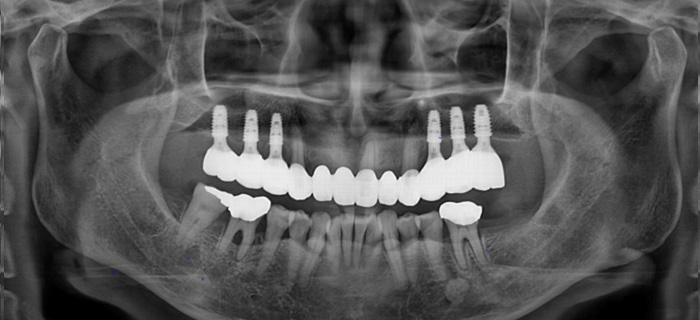

오래가고 튼튼한 임플란트 결과로 증명합니다.

최신식 3D장비로 식립 전후를

확인할 수 있습니다.